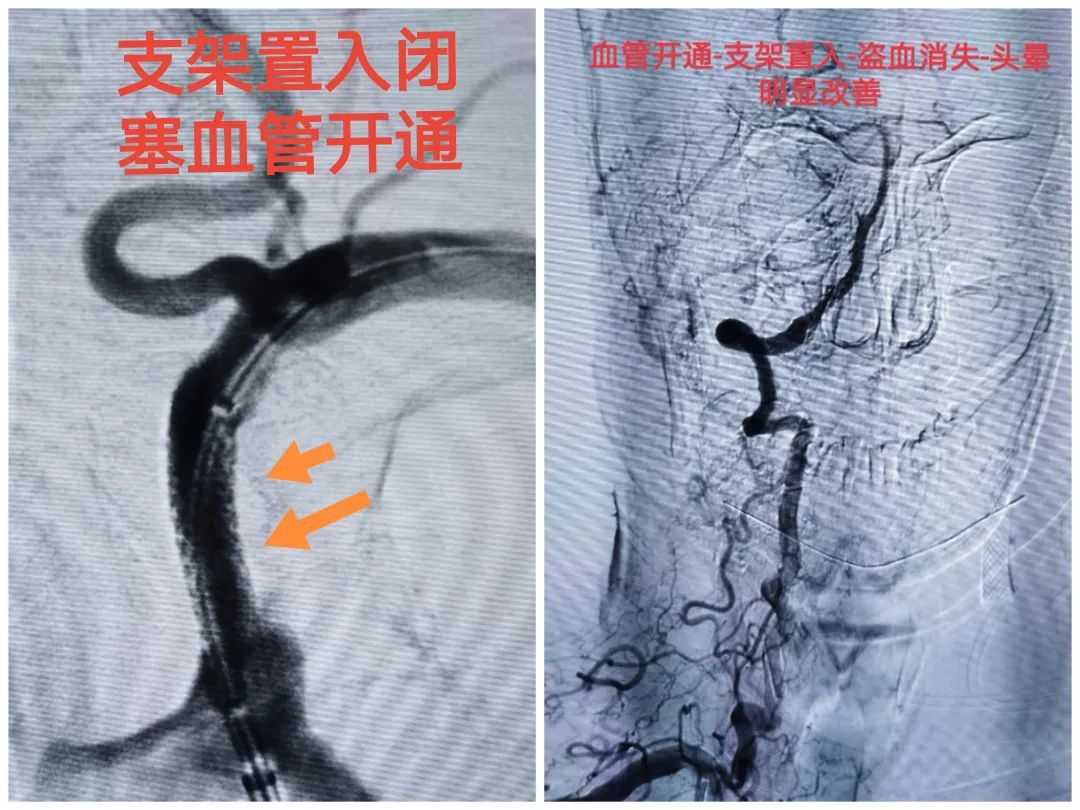

除了内科治疗外,若缺血症状严重可以考虑手术治疗,如血管内支架、血管内膜剥离或血管重建术等,其中对于症状性锁骨下动脉狭窄≥50%患者,血管内支架治疗是首选的治疗方法。

请点击输入图片描述